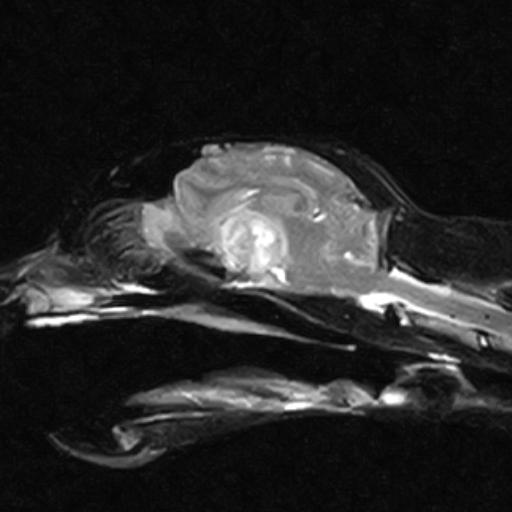

In order to diagnose brain tumours, CT-scans or MRI-scans are used to image the brain. Despite the fact that these tests are very good at detecting the presence of a mass in the brain, they are very poor at identifying its exact nature (i.e. whether it is a tumour, inflammation, or bleeding within the brain).

When it comes to people, a biopsy of a brain tumour is the preferred way to determine the type of tumour and other information regarding treatment and prognosis. Normally, we do not recommend brain biopsy in animals since it is a very invasive and potentially risky procedure. A veterinary neurologist will often diagnose a tumour type based on key features on scans. This approach has limitations, so it is difficult to provide accurate information regarding treatment and prognosis.

Secondary brain tumours: Tumours can grow from tissue surrounding the brain, either pressing on or infiltrating the brain such as nasal or ear tumours and tumours of the skull.